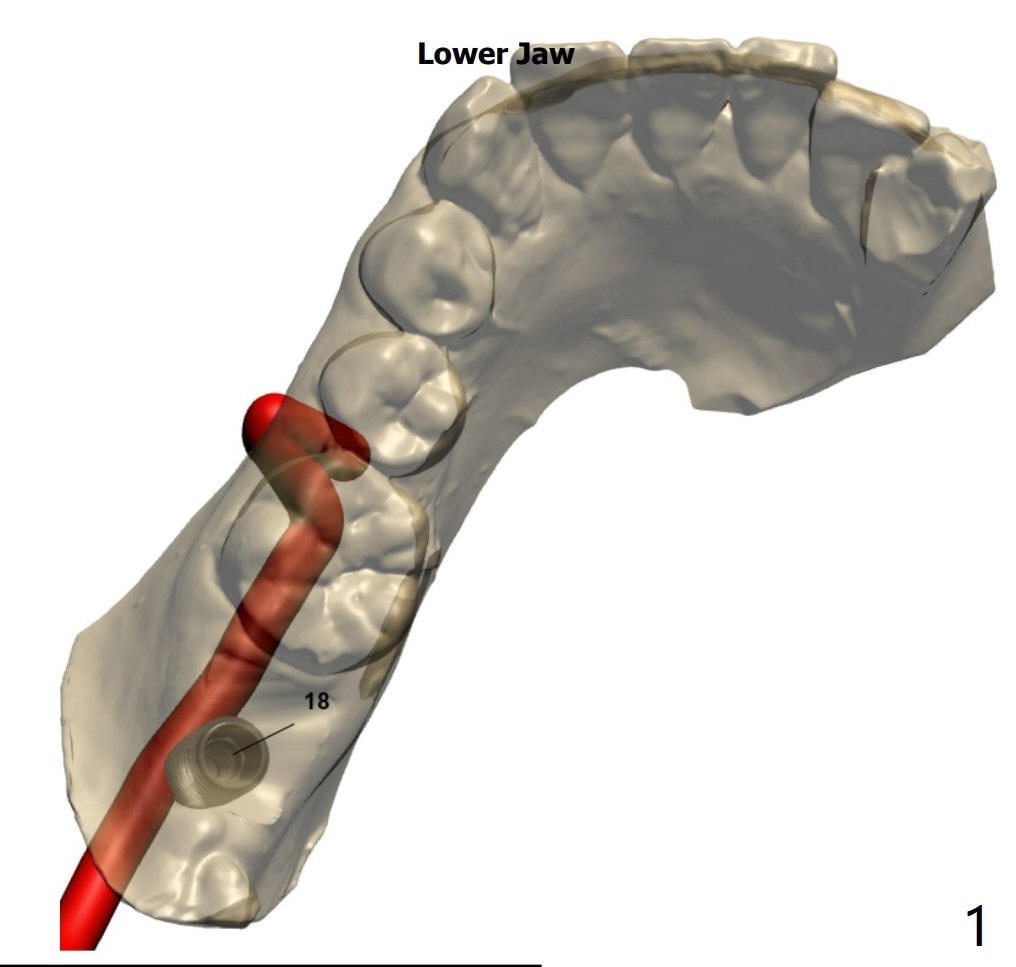

左下7植体设计

先将2.2mm钻头逐渐抵达深度,拍摄根尖片,完成种植和放置基台后,再拍摄根尖片,比较是否钻洞偏移远中。植体植入稍微浅些。